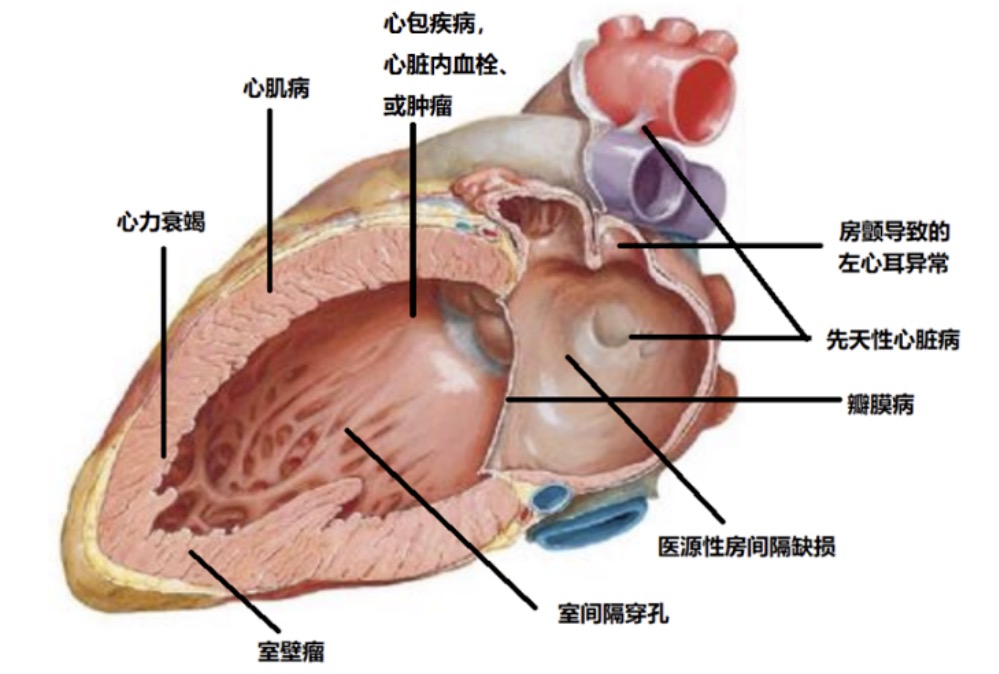

对于结构性心脏病来说,主要包括先天性、瓣膜性心脏病、心肌病及大血管疾病等。

其他

-

心肌病(肥厚性心肌病、扩张型心肌病等) -

并发于其它疾病或者外源性的心脏结构异常(室间隔穿孔、室壁瘤、医源性房间隔缺损等) -

并发于其它疾病的导致心脏功能的异常并通过改变心血管结构可得到纠正的疾病或状态(如房颤导致左心耳功能异常,心力衰竭导致心脏功能的异常) -

其他更不常见的疾病:如心脏内血栓、心脏肿瘤、心包疾病等。